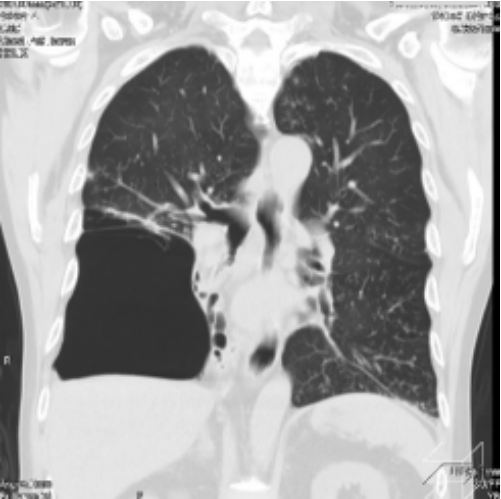

CT显示肺大泡压迫了右肺中叶和下叶,导致肺不张

;但是,右肺上叶充气良好(图2)。

图2. CT显示肺大泡压迫了右肺中叶和下叶,导致肺不张;但是,右肺上叶充气良好